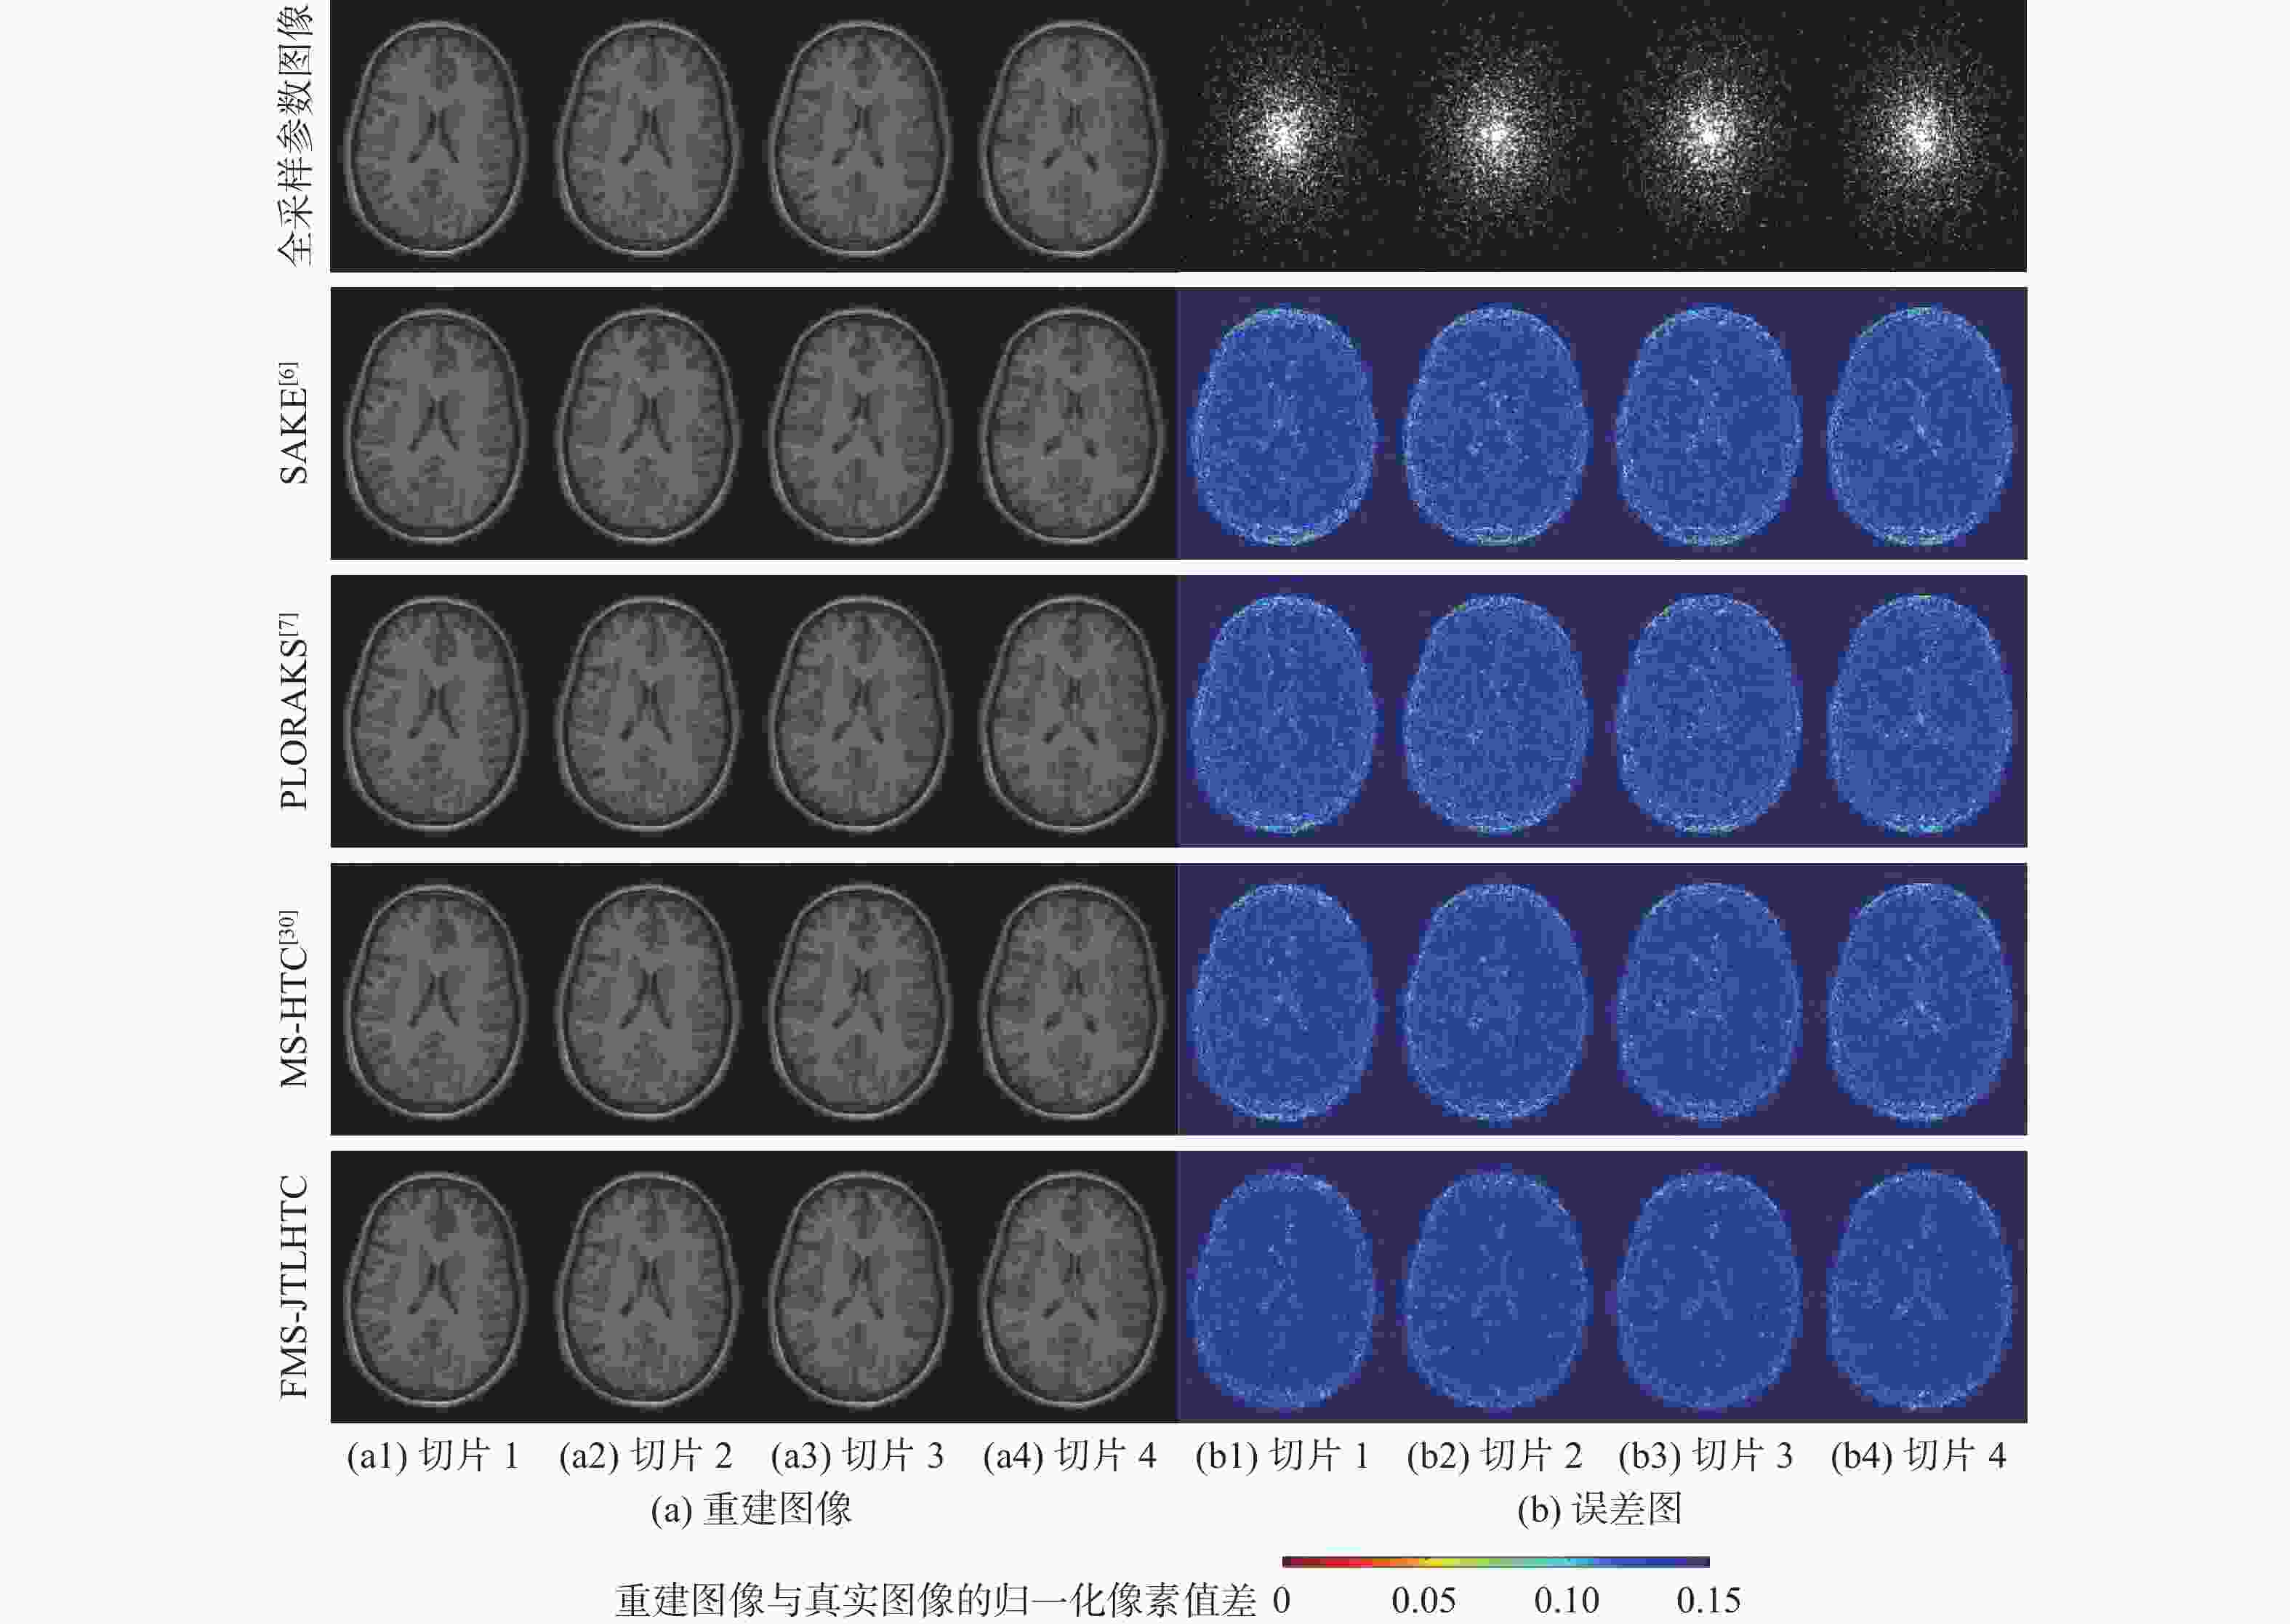

二维(2D)多切片磁共振数据在相邻切片之间具有高度的相关性,通过利用切片间的冗余性能够重建出更高质量的切片图像,但由于硬件条件的限制,2D多切片磁共振成像(MRI)需要耗费大量时间。为提高2D多切片磁共振图像的重建质量和重建速度,将联合稀疏变换学习正则项引入到多切片Hankel张量完成(MS-HTC)模型中,提出一种快速2D多切片磁共振成像重建(FMS-JTLHTC)算法。该算法使用交替方向乘子法对目标问题进行求解;引入快速迭代收缩阈值法加快收敛,并使用图形处理器对算法进行加速。使用4组脑部数据集在2种不同采样模式下进行实验,结果表明:FMS-JTLHTC算法的峰值信噪比(PSNR)相较于同时自动校准和K空间估计(SAKE)算法、并行成像数据的局部K空间领域的低秩建模(PLORAKS)算法和MS-HTC算法分别平均提高了4.04 dB、3.67 dB和2.07 dB,而且重建速度相比MS-HTC算法提高了14倍。

Abstract:Due to the significant correlation between neighboring slices in two-dimensional (2D) multi-slice magnetic resonance data, higher quality slice pictures can be reconstructed by taking use of the redundancy between slices. However, 2D multi-slice magnetic resonance imaging requires an amount of time. To improve the reconstruction quality and speed of 2D multi-slice (MRI) images, proposes a fast 2D multi-slice MRI reconstruction (FMS-JTLHTC) algorithm, which introduces the joint transform learning regular term into the multi-slice hankel tensor completion (MS-HTC) model. Prior to introducing the fast iterative shrinkage-thresholding procedure to accelerate convergence and utilize the graphics processing unit to speed up the procedure, the alternating direction method of multipliers is used to solve the objective issue. Experiments using four brain datasets in two different sampling modes show that the peak signal-to-noise ratio (PSNR) of the FMS-JTLHTC algorithm is improved by an average of 4.04 dB, 3.67 dB, and 2.07 dB compared to the simultaneous atuo-calibrating and K-space estimation (SAKE), low-rank modeling of local K-space neighborhoods with parallel imaging data (PLORAKS) and MS-HTC algorithms, respectively, the reconstruction speed is improved by a factor of 14 compared to the MS-HTC algorithm.